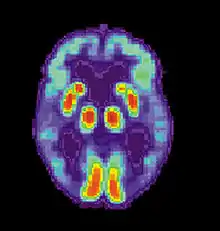

PET scan of a healthy brain - Image courtesy of US National Institute on Aging Alzheimer's Disease Education and Referral Center PET scan of brain with AD - Image courtesy of US National Institute on Aging Alzheimer's Disease Education and Referral Center

PET scan of brain with AD - Image courtesy of US National Institute on Aging Alzheimer's Disease Education and Referral Center

Alzheimer's disease (AD) is a progressive, degenerative and fatal brain disease, in which cell to cell connections in the brain are lost. Alzheimer's disease is the most common form of dementia.[2] Globally approximately 1–5% of the population is affected by Alzheimer's disease.[3] Women are disproportionately affected by Alzheimer's disease. The evidence suggests that women with AD display more severe cognitive impairment relative to age-matched males with AD, as well as a more rapid rate of cognitive decline.[4]